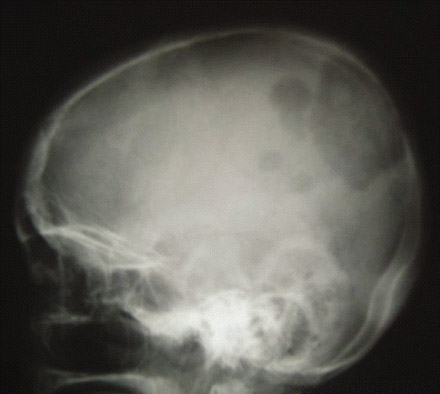

El carcinoma papilar tiende a extenderse a los ganglios linfáticos locales, mientras que el carcinoma folicular y el carcinoma oncocítico se extienden más a menudo por vía hematógena. El carcinoma anaplásico de tiroides es agresivo con una alta propensión a la invasión local y a la diseminación metastásica. La diseminación ganglionar es frecuente en los linfomas tiroideos primarios.[Figure caption and citation for the preceding image starts]: Radiografía de cráneo que muestra metástasis extensa de un carcinoma folicular de tiroidesWani AM, Hussain WM, Fatani MI, et al. Skull metastases from thyroid carcinoma. BMJ Case Reports. 2009; doi:10.1136/bcr.02.2009.1578 [Citation ends].